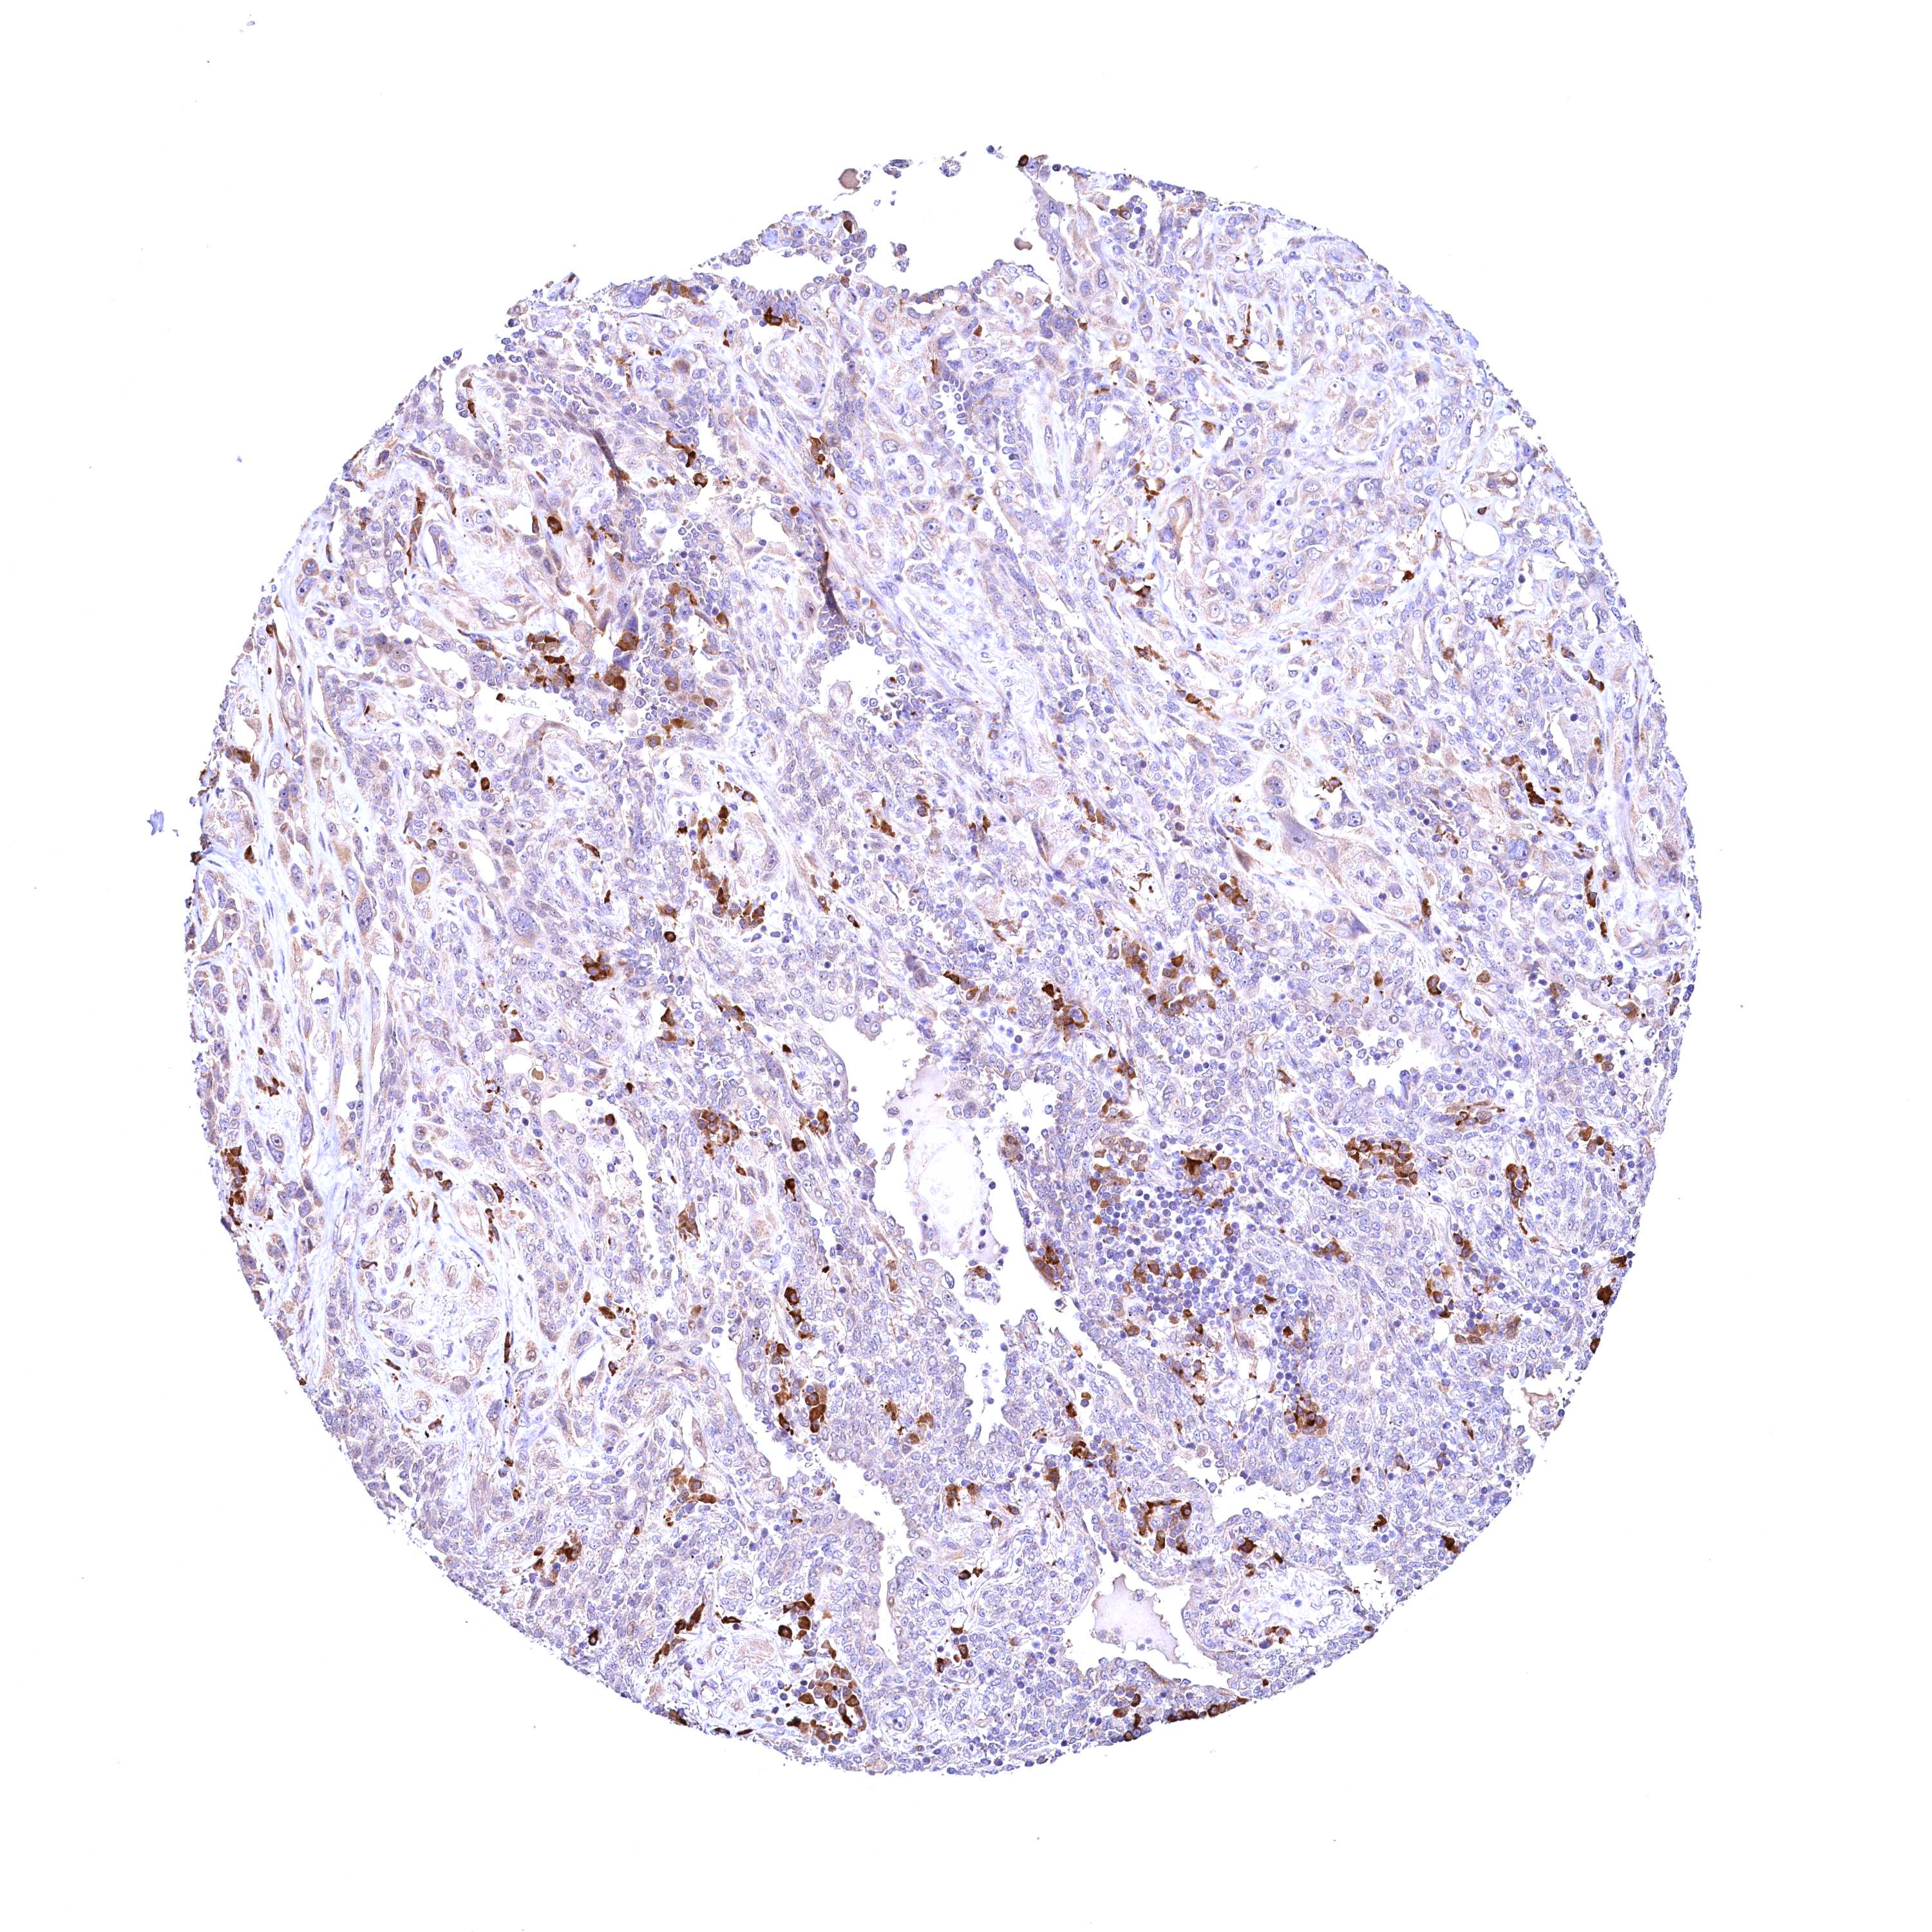

CANCER LUNG CANCER Show tissue menu

Lung cancer

Human cancer

Lung adenocarcinoma

RBFA is not prognostic in Lung Adenocarcinoma (TCGA)

Average pTPM 15.8

Number of samples 497